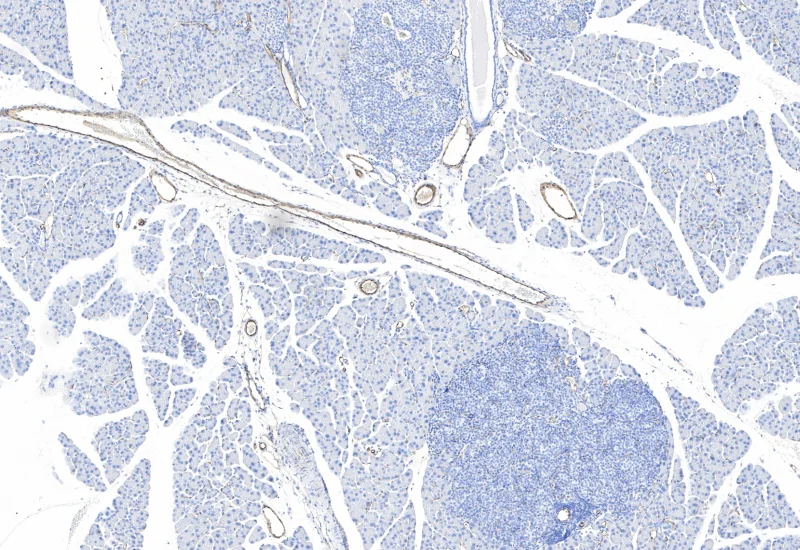

IHC Tumor Vascularization

The IHC Tumor Vascularization APP provides tissue detection including the separation into tumor tissue and healthy tissue (or tumor stroma). It additionally detects blood vessels based on appropriate stains (e.g. CD31) and measures number and area of the blood vessels. The vessel detection also can be set to close open stained vessel walls and to connect separated vessel sections within a definable distance. The APP outputs number and vessel density as well as areas of vessels, within tumor tissue and healthy tissue.

Image courtesy of Dr. Patrick Michl, Dr. Maren Egidi and Dr. Heidi Griesmann, Universitätsklinikum Halle (Saale).